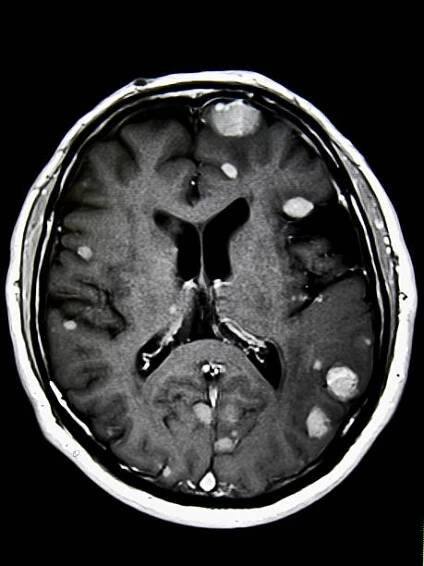

Mozkové metastázy jsou sekundární – druhotné nádory mozku, jejichž původem jsou nádory jinde v těle. Nejčastěji do mozku a míchy metastazují karcinom plic, ledvin, u žen karcinom prsu, a dále zhoubný melanom.

Mozkové metastázy jsou častou komplikací systémových nádorových onemocnění, z nichž 60–75 % se v průběhu života stává symptomatickými.